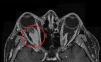

A 47 year-old woman with a background of total thyroidectomy from goitre with benign thyroid nodules presented with exophthalmos of several weeks onset (Fig. 1). There was no involvement of the ENT sphere, and no pulmonary, polyneuropathy, dry syndrome, arthralgias, photosensitivity or cutaneous lesions. Magnetic resonance (MR) imaging revealed a solid retrobulbar mass which surrounded the optic nerve and was of fusiform morphology measuring 24×9mm (Fig. 2). We considered the need for biopsy but desisted, due to the high risk of complications. The ANAS, ANCAS, anti-DNA analysis, complement activity, proteinuria and ACE tested negative and the raising of immunoglobulin G4 860mg/dl was remarkable (normal: 10–140). The patient was diagnosed with a possible IgG4-related inflammatory orbital disease in keeping with clinical and serological criteria. Treatment with high doses of steroids and azatiorpine was initiated but suspended due to intolerance. The patient is currently being treated with mycophenolate mofetil and is responding favourably with no inflammatory activity. IgG4-related disease is a new entity which comprises several fibroinflammatory diseases which have not been previously linked to one another.1,2 Clinical features are highly varied and presentation is usually subacute.3,4 Ocular-orbital symptoms include: idiopathic orbital inflammation, pachymeningitis and sclerouveitis.5,6 Orbital pseudotumour is an uncommon presentation of IgG4 diseases.7 It is important to recognize this new disease to diagnoses it, since specific treatment may prevent complications.